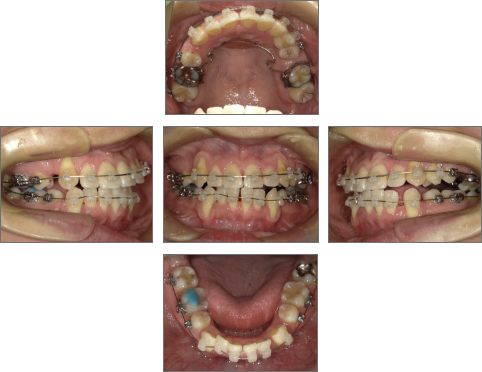

【治療経過】

●主訴

歯並びのガタガタが気になる。歯磨きがしづらく、将来、歯が悪くなってしまうのではないか、心配。

●診断名あるいは主な症状

叢生

●年齢

31歳2ヶ月

●治療に用いた主な装置

セラミックブラケット

●抜歯部位

右上4番、左上6番、右下4番、左下4番・8番(親知らず) 計5本抜歯

●治療期間

約2年